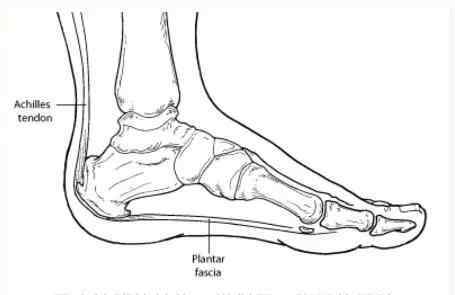

中老年患者,甚至是年轻人,抱怨脚后跟疼痛,影响走路。拍完x光片,没有异常,只有轻微骨刺。排除其他具体疾病后,多数病例为足底筋膜炎。

足底筋膜炎的疼痛特点:脚跟下刺痛,可延伸至前脚。早上走路的时候,前几步疼痛明显,走几分钟就缓解了。不活动后重复。

正常的足弓和足底筋膜的结构类似于弓和弓弦。负重站立时,足弓下压,弓弦绷紧,压力增大。持续的异常牵引刺激会导致弓弦止点无菌性炎症。

适当休息数周,调整行走方式,避免久站和长时间走路。若无禁忌,可口服布洛芬或双氯芬酸钠、塞来昔布等药物止痛。足底踩在啤酒瓶上滚动几分钟,每天至少2次,2-8周,缓解足弓疼痛。用鞋垫或足弓垫支撑足弓,缓解疼痛。可用一小块纱布垫在足心。

足跟痛拉伸练习

足底筋膜拉伸

坐姿,用手掰前脚掌,勾到脚背,被动拉伸脚趾。

腿部伸展

你需要用手弯曲你的臀部和膝盖。如果觉得累,可以采用坐姿或卧姿,双腿伸直,用毛巾勾住脚趾和前脚掌,将毛巾拖到身体上,使双脚向后弯曲。

小腿后肌群牵引

站立膝关节伸直弯曲,重点是腿后肌肉群的牵拉活动。